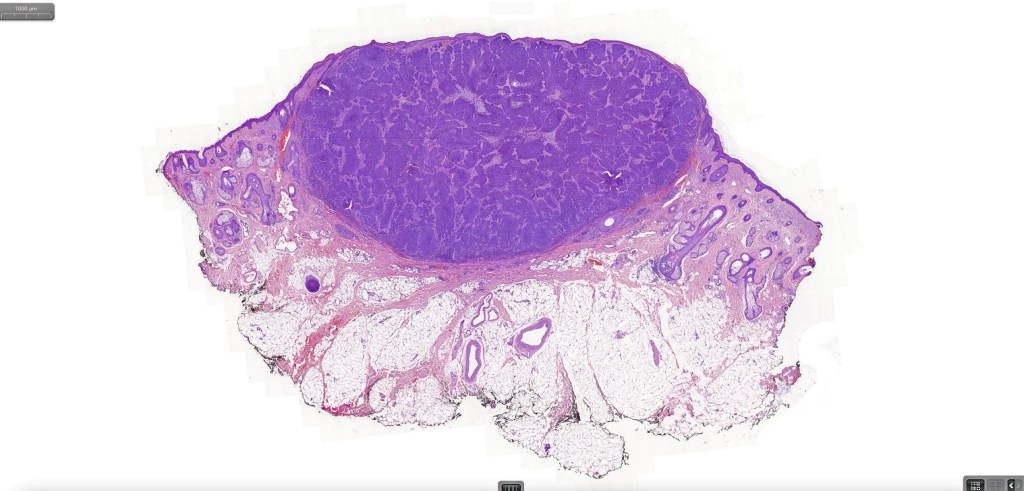

Histological features

•Both epithelial & fibrous stromal components

•The tumor commonly arises from the epidermis

•The epithelial component is composed of uniform small, basophilic devoid of desmosomes

•Peripheral palisading

•Retraction artifact with stromal mucin

•A wide variety of histological variants are possible including nodular, nodulocystic, ulcerative, superficial, micronodular, infiltrating/infiltrative, keratotic, basosquamous, pigmented, morpheaform, keloidal, clear-cell, signet-ring cell & granular cell variants, BCC with monster cells, BCC with metaplastic features, BCC with matricial differentiation, basomelanocytic tumor (see separate blog), BCC with thickened basement membrane, BCC with carcinoid-like nuclear palisading & these are illustrated below